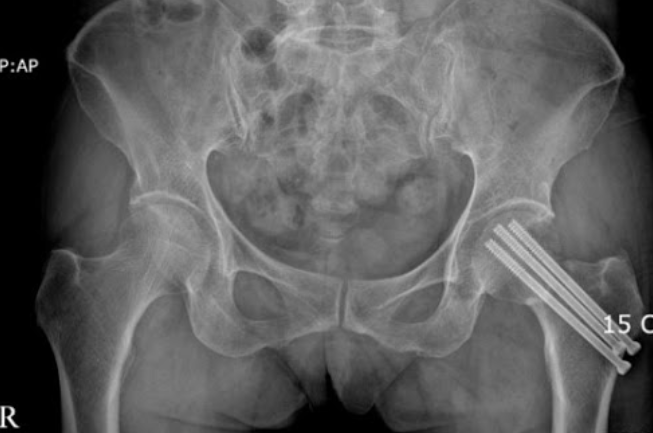

고관절 수술방법으로는 보통 3가지 방법으로 나뉩니다. 첫번째로는 대퇴골두에만 구멍을 뚫어 혈관이 생설될 수 있는 통로를 만들어 자기 관절을 살리는 감압술을 하는 방법이 있습니다.